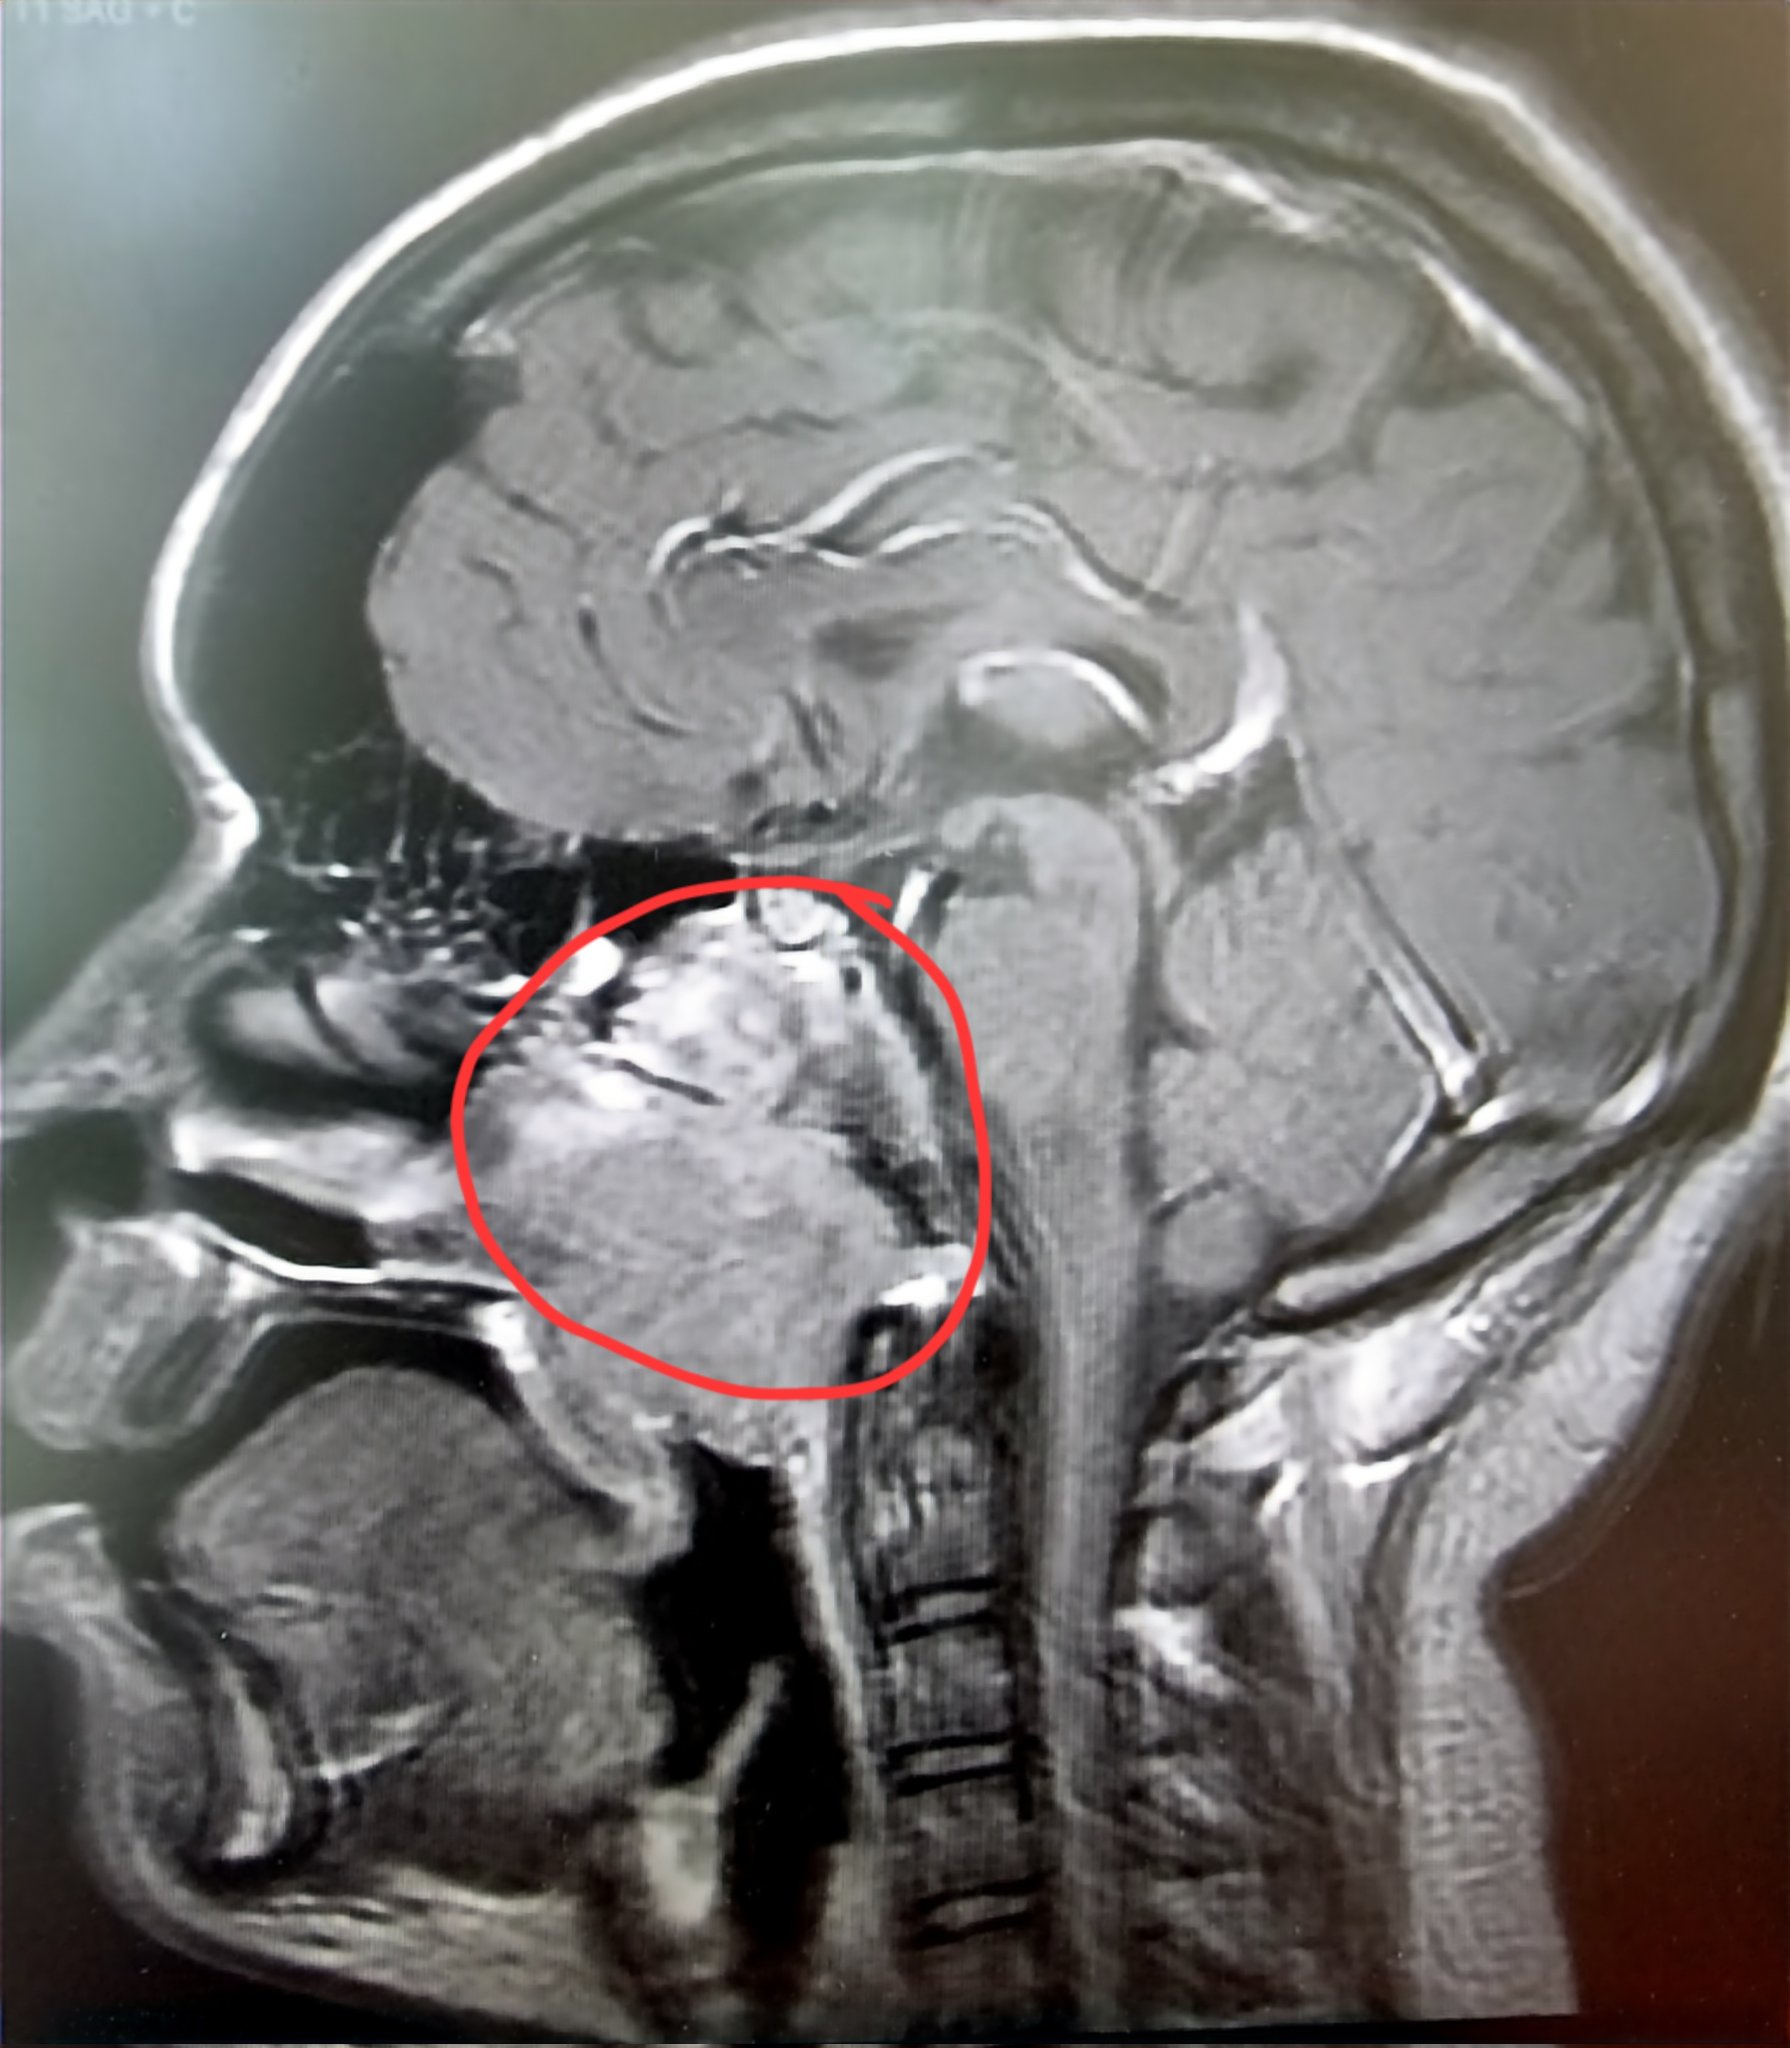

. Kanser otak tahap 4 Saturday March 5 2022 Edit. Perkembangan penyakit ini terbahagi kepada empat tahap yang lebih dikenali sebagai barah otak tahap 1 2 3 atau 4. Secara umumnya kanser otak dinilai bermula daripada tahap 1 sehingga 4 tahap ini akan diklasifikasikan mengikut tahap kecepatan mereka berkembang dan bagaimana mereka.

Secara umumnya kanser otak dinilai bermula daripada tahap 1 sehingga 4 tahap ini akan diklasifikasikan mengikut tahap kecepatan mereka berkembang dan bagaimana mereka. Oleh itu bagaimana setiap peringkat ini menjelaskan. Kanser tahap 4 merupakan pengkelasan kanser dengan kedudukan yang paling tinggi ia biasanya memiliki kemampuan untuk menyerang metastasis organ lain kebarangkalian untuk sembuh.

Hidup Nor Fizi 45 tahun berubah 360 darjah selepas doktor mengesahkannya menderita kanser otak. CABARAN SEBAGAI KETUA KELUARGA DENGAN DERITA KANSER OTAK TAHAP 4. Adik Zikri di diagnos dengan Kanser Otak Tahap 4.